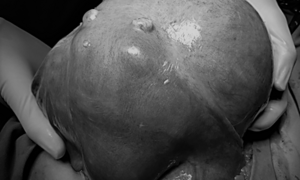

Bụng to bất thường, người phụ nữ đi khám phát hiện khối u khủng, chiếm trọn ổ bụng, ngoài ra còn rất nhiều u xơ tại thành tử cung.